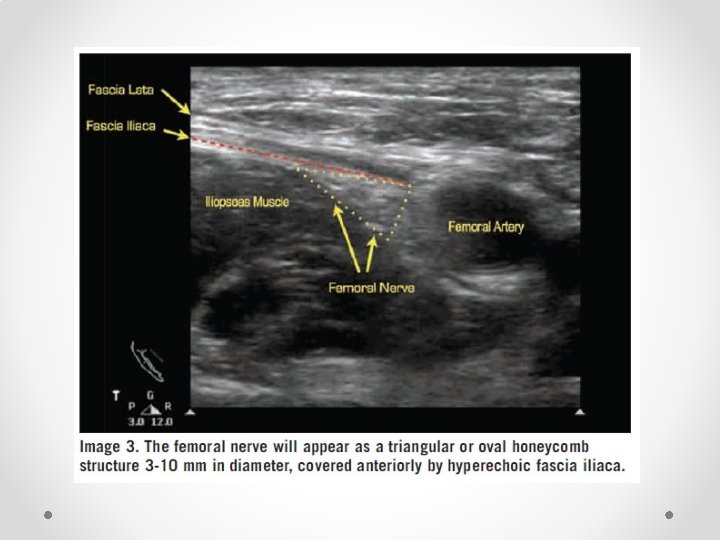

Femoral Nerve block • Not commonly done for chronic pain • Fairly well known block so only short mention of some reminders • Book first on list, use lignocaine as quads weakness means falls risk • Note fascial planes: o Nerve is NOT in same plane as femoral vessels o Nerve lies deep to fascia iliaca, while vessels lie superficial o Nerve is often difficult to see on ultrasound, while artery is easy to see • Therefore aim for needle tip to be lateral and deep relative to the artery to be in the correct plane